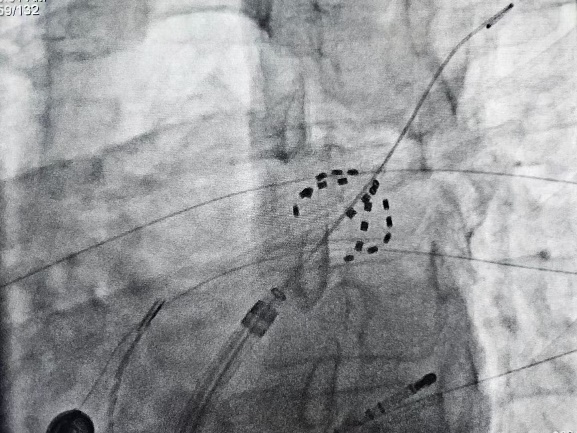

手术过程在三维导航系统辅助下精确实施,操作时间短,创伤小,患者术中舒适度高。FARAPULSE系统以非热能方式工作,避免了传统消融可能引起的心房食管瘘、膈神经损伤等并发症,同时确保高效消融效果。术后标测显示,患者肺静脉实现了完全电隔离,手术取得了圆满成功。

FARADRIVE导管以网篮和花瓣两种形态进行肺静脉消融